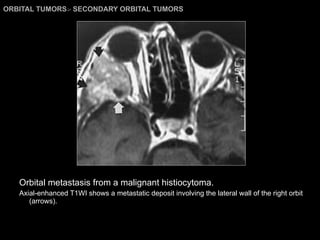

SECONDARY ORBITAL TUMORS Directly invasion. From sinonasal cavities, oral cavity, skin of face and intracranial.  Metastases to the orbit. Women : CA breast. Men: CA lung, kidney, or prostate.  Children: Primary neuroblastoma, Ewing’s sarcoma, and Wilms’ tumor.   Metastatic lesions may occur in any of the orbital compartments. CT and MRI findings: may simulate benign and malignant orbital tumor.

ORBITAL TUMORS >  SECONDARY ORBITAL TUMORS Orbital metastasis from a malignant histiocytoma. Axial-enhanced T1WI shows a metastatic deposit involving the lateral wall of the right orbit (arrows).